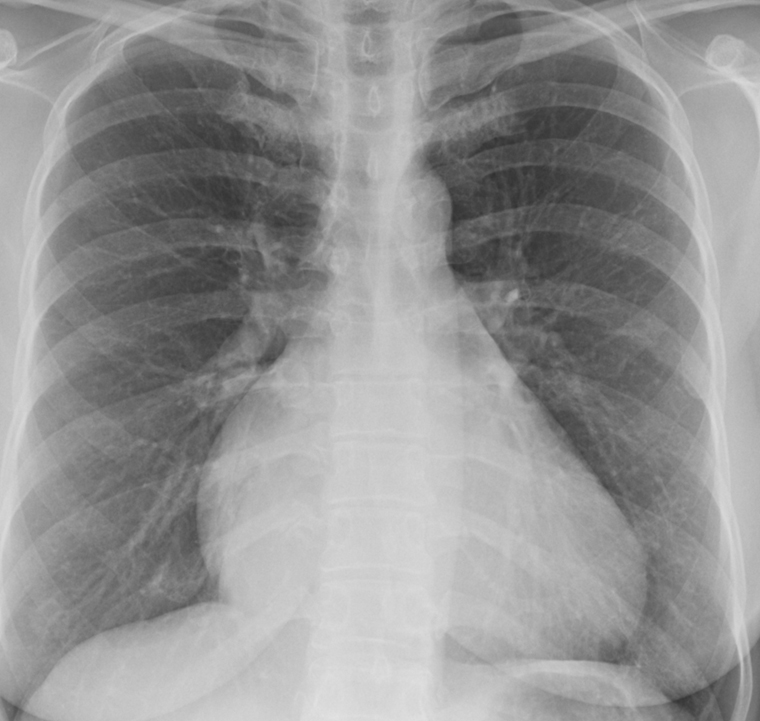

Tricuspid insufficiency PA